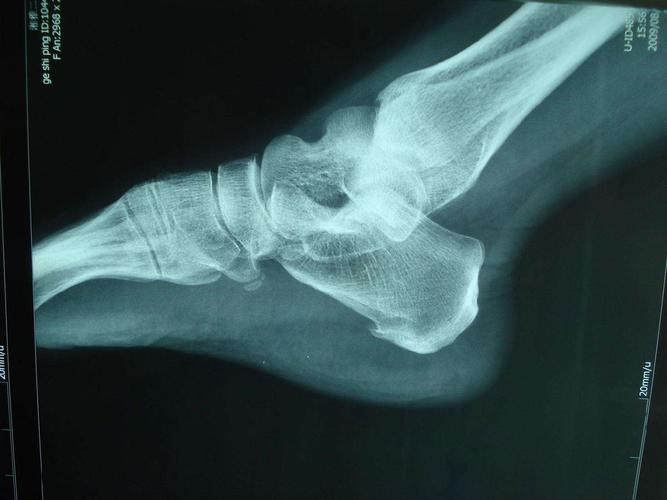

(后足力线看着几乎正常,文献上许多nwd是后足内翻) 3.

足x线的正常表现及常见病变